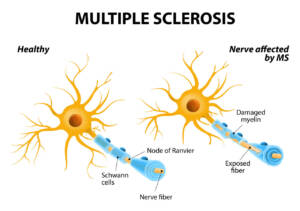

Nelle malattie degenerative: per il trattamento di sclerosi multipla,

SLA,